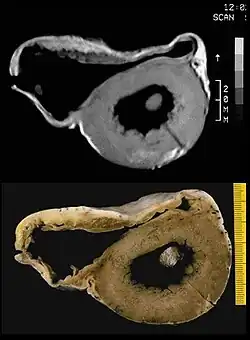

There are two pathological patterns seen in ACM, Fatty infiltration and fibro-fatty infiltration.

Fatty infiltration

At first, fatty infiltration, is confined to the right ventricle. This involves a partial or near-complete substitution of myocardium with fatty tissue without wall thinning. It involves predominantly the apical and infundibular regions of the RV. The left ventricle and ventricular septum are usually spared. No inflammatory infiltrates are seen in fatty infiltration. There is evidence of myocyte (myocardial cell) degeneration and death seen in 50% of cases of fatty infiltration.

Fibro-fatty infiltration

The second, fibro-fatty infiltration, involves replacement of myocytes with fibrofatty tissue. A patchy myocarditis is involved in up to 2/3 of cases, with inflammatory infiltrates (mostly T cells) seen on microscopy. Myocardial atrophy is due to injury and apoptosis. This leads to thinning of the RV free wall (to < 3 mm thickness) Myocytes are replaced with fibrofatty tissue. The regions preferentially involved include the RV inflow tract, the RV outflow tract, and the RV apex. However, the LV free wall may be involved in some cases. Involvement of the ventricular septum is rare. The areas involved are prone to aneurysm formation.

A post mortem histological demonstration of full thickness substitution of the RV myocardium by fatty or fibro-fatty tissue is consistent with ACM.